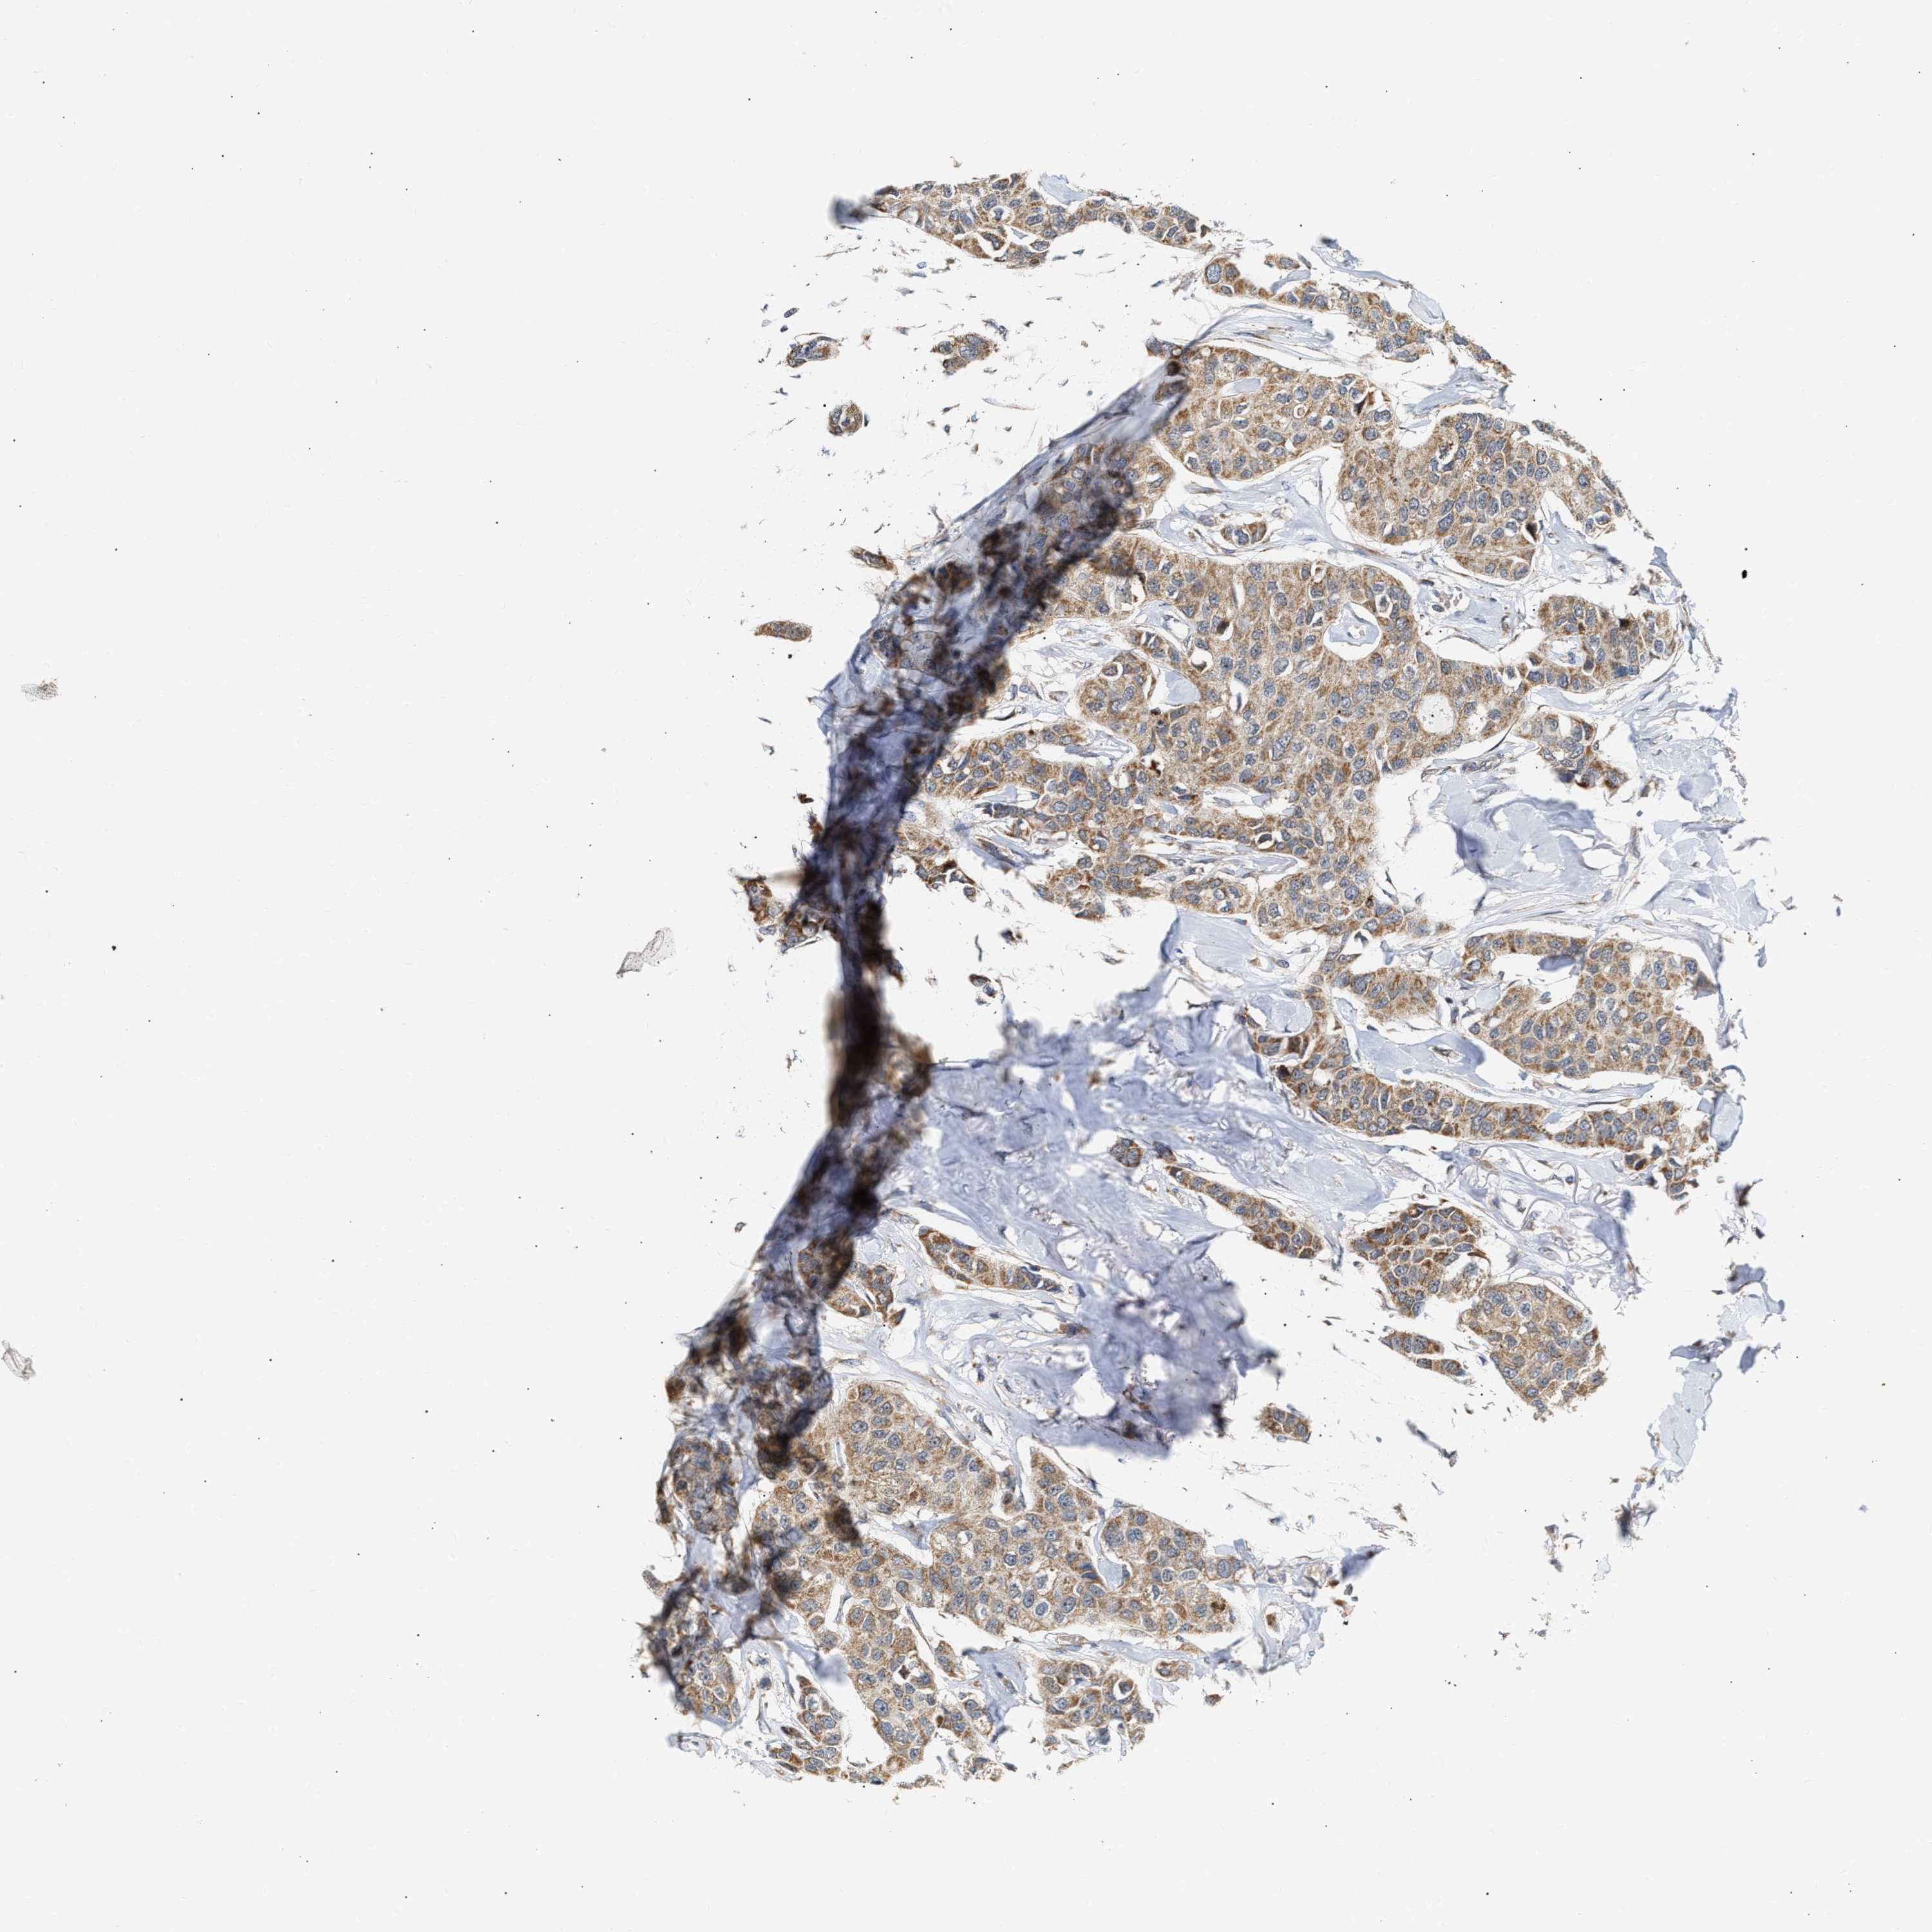

CANCER BREAST CANCER Show tissue menu

BRCA TCGA BRCA VALIDATION PROTEIN EXPRESSION